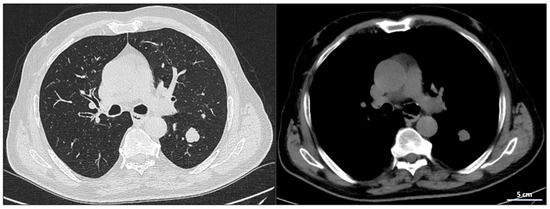

At the radiological follow-up in July 2024, imaging demonstrated sustained disease stability, with no new pleural effusions and stable lymph nodes. These findings confirmed a prolonged response to atezolizumab, representing a rare case of long-term disease control in advanced-stage small-cell lung cancer (SCLC), with some lymph nodes completely resolving and others reduced to clinically insignificant sizes. At the most recent radiological follow-up performed on 10 March 2025, total-body CT imaging confirmed continued disease stability. No evidence of recurrence was observed in the thoracic region, and there were no new lesions detected either in the lungs or at extra-pulmonary sites. This further supports the sustained response to maintenance immunotherapy with atezolizumab.

Serial CT and PET-CT scans over a 24-months period confirmed the absence of new lesions and sustained tumor control. Lymph node involvement, initially extensive, showed significant regression, with some nodes completely resolving. This case suggests that, in select patients, chemo-immunotherapy may induce durable responses beyond standard expectations, warranting further investigation into predictive biomarkers (Figure 5 and Figure S3).

Figure 5.

Reduction of mediastinal lymphadenopathy during treatment with combination therapy and maintenance with atezolizumab.